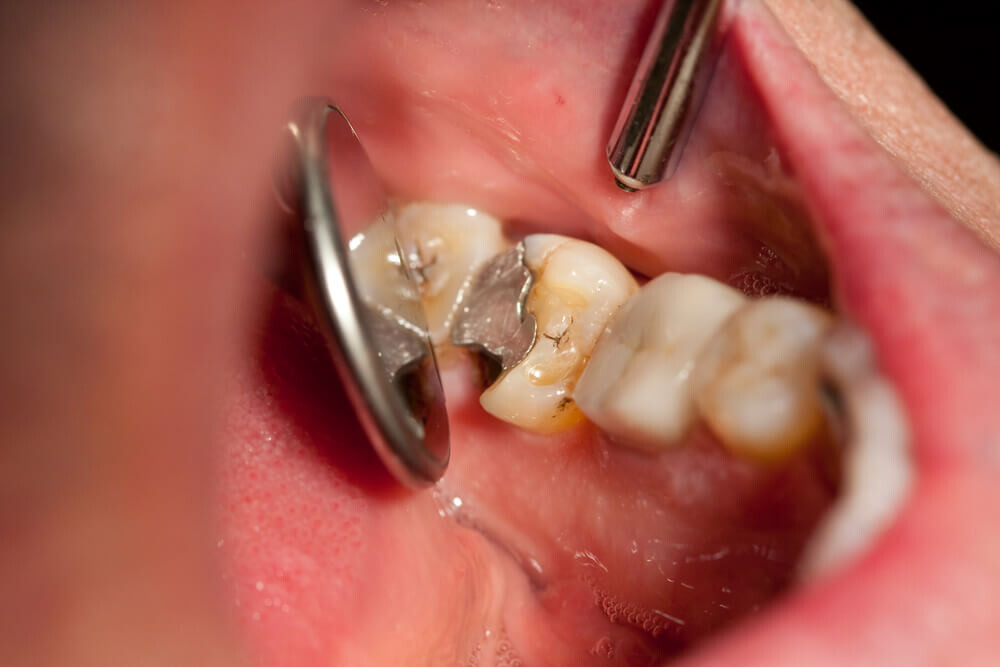

Tooth decay

As tooth decay progresses, it can reach the softer inner layers of the tooth, called dentin and pulp, resulting in sensitivity to hot, cold, or sweet foods and drinks and eventually leading to a toothache. If left untreated, tooth decay can result in an abscess, a painful infection at the root of the tooth that can cause severe pain and swelling. Adhering to your routine dental check-ups, practicing good oral hygiene, and eating a healthy diet can help prevent tooth decay and the resulting toothache.

A damaged filling

A damaged filling can cause toothache when the filling is no longer able to protect your tooth from external stimuli. When a filling is damaged, it can create an opening in the tooth, allowing bacteria to penetrate and cause an infection, leading to inflammation, swelling, and pain. Additionally, if you don’t replace the filling in time, it may cause your tooth to weaken or crack. A damaged filling may also cause sensitivity to hot and cold food and drinks.

What does a cavity feel like? In the earliest stages, the answer might be nothing. There are no nerves in your tooth enamel, so when the decay is in that layer, you likely won't feel a thing. Once the decay has progressed enough to reach the softer tissues inside the tooth, where the dentin and nerves are, you might notice signs of a cavity. Your teeth might feel sensitive and you could feel some pain, especially after eating sweets, hot foods or cold foods. The pain can be fairly mild or sharp and intense. Some people with cavities also feel pain when biting down.

Depending on the size of the cavity, you may be able to see evidence of it in your mouth. Cavities sometimes create visible holes in the teeth. They can also create stains that are black, brown or white on the surface of the tooth.